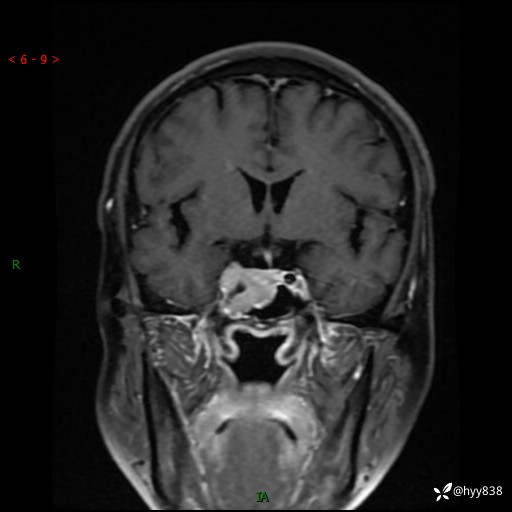

规培和研究生教学片:鞍旁占位,脑膜瘤 VS 侵袭性垂体瘤---结果公布~

现病史:患者半年前无明显诱因出现头痛头痛,呈间断性发作,无复视,无斜视,无头痛头晕,无呕心呕吐,无肢体乏力,无发作性肢体抽搐,无意识改变,无尿量增多,无体毛脱落,无色素沉着,无体重下降,无面容改变,无肢端粗大等,2024-03-26日至当地中医院住院治疗后予以对症处理(具体不详),未见明显缓解,行头颅MRI平扫检查示:“右侧蝶鞍占位,双侧上颌窦炎,双侧下鼻甲肥大,鼻中隔偏曲”,今患者为求进一步诊治来我院,门诊遂以“右侧蝶鞍占位”收住我科。 起病以来,患者精神饮食睡眠可,大小便正常。

MRI增强(外院平扫)